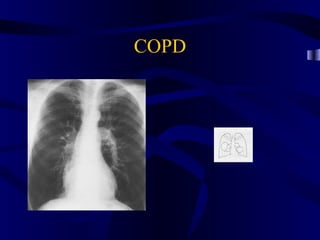

COPD

• 74.